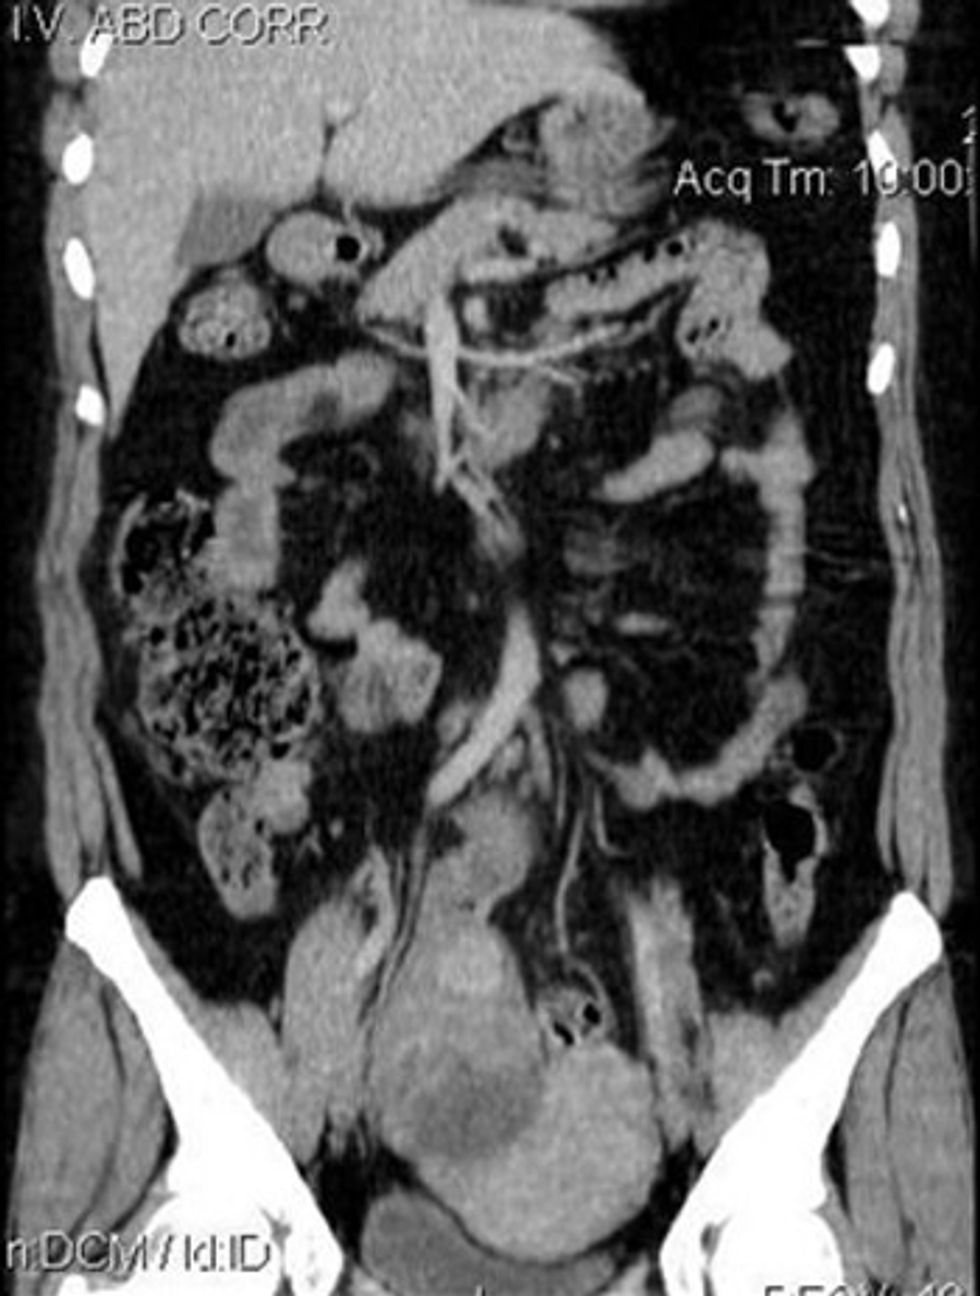

Organet abdominale mund të paraqiten përmes rekonstruimeve në të tre rrafshet dhe analizohen ndryshimet e mundshme në formën dhe sipërfaqen e tyre.